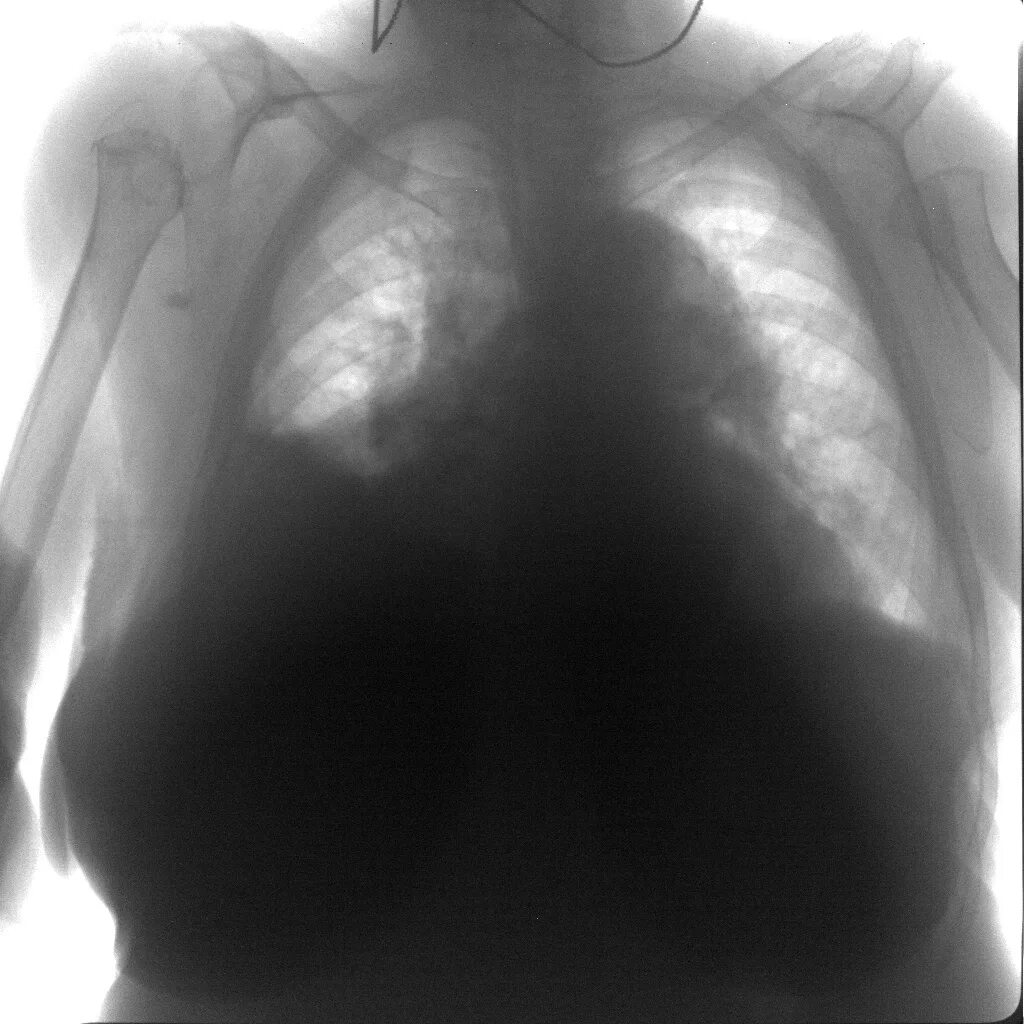

Гидроторакс мкб 10 у взрослых